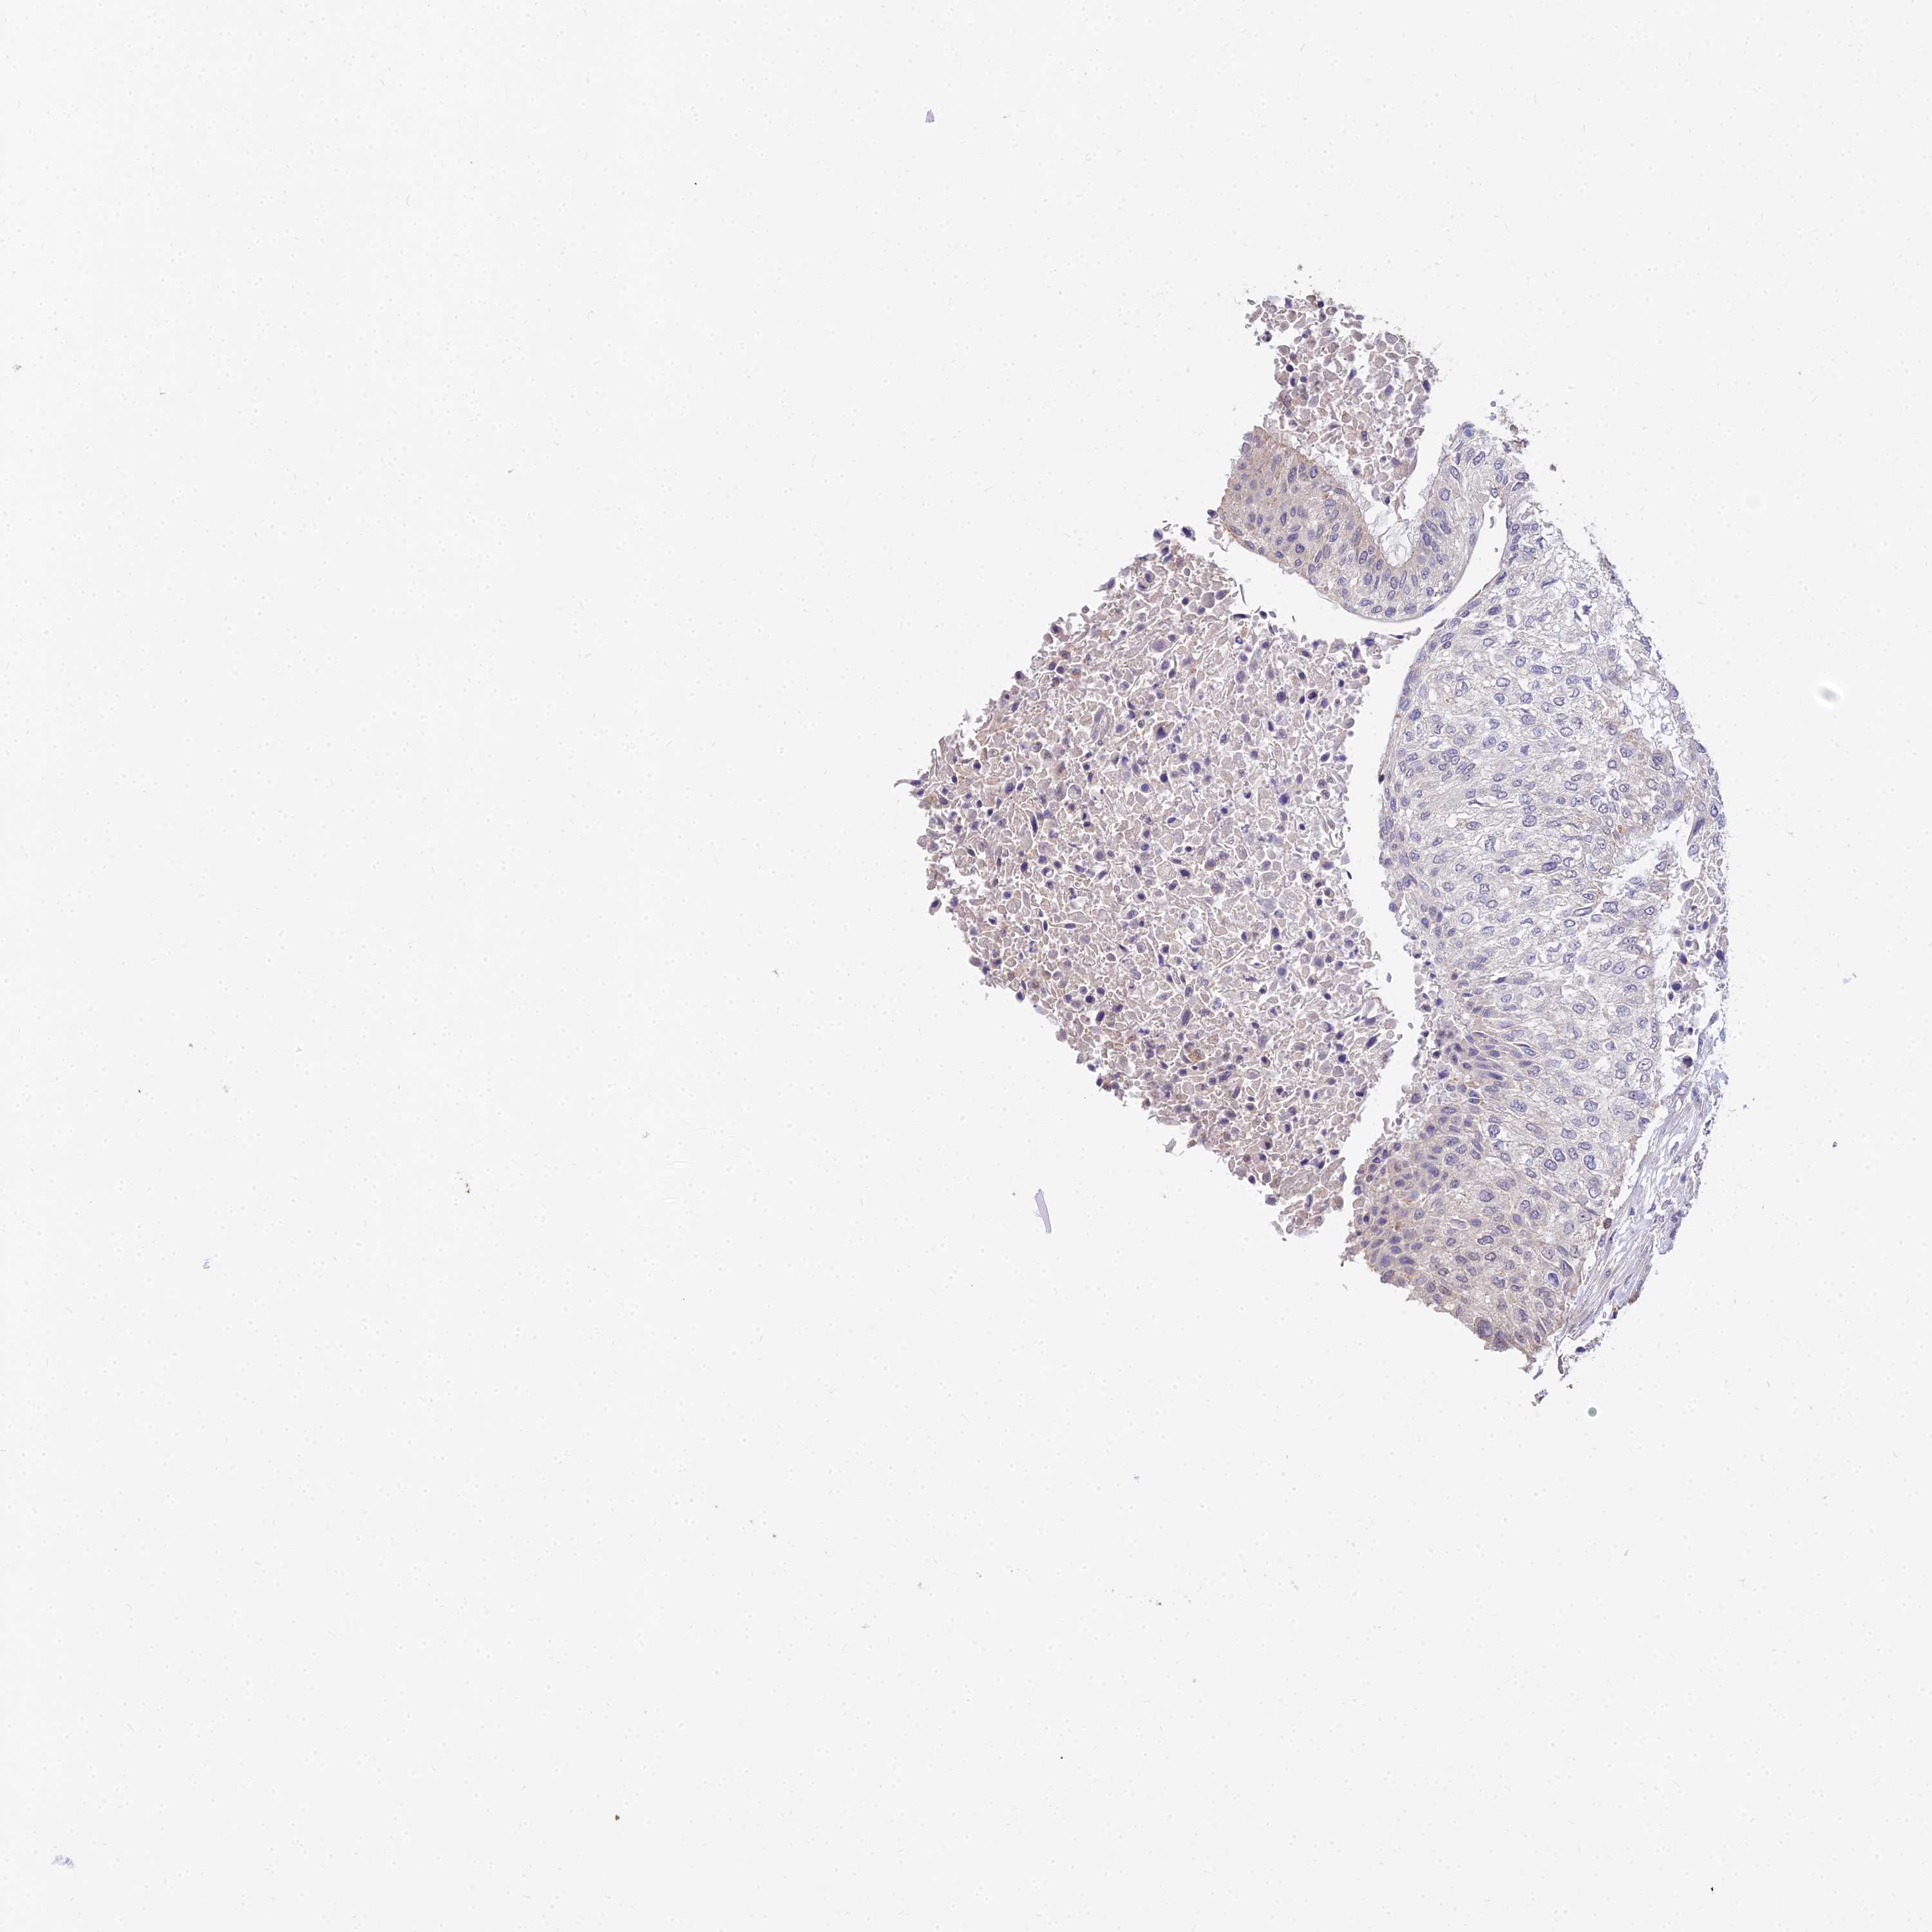

UROTHELIAL CANCER - Protein expressioni

A mouse-over function shows sample information and annotation data. Click on an image to view it in a full screen mode. Samples can be filtered based on level of antibody staining by selecting one or several of the following categories: high, medium, low and not detected. The assay and annotation is described here.

Note that samples used for immunohistochemistry by the Human Protein Atlas do not correspond to samples in the TCGA dataset.

Antibody stainingi

Antibody staining in the annotated cell types in the current human tissue is reported as not detected, low, medium, or high, based on conventional immunohistochemistry profiling in selected tissues. This score is based on the combination of the staining intensity and fraction of stained cells.

Each image is clickable and will lead to virtual microscopy that enables deeper exploration of all samples and also displays staining intensity scores, fraction scores and subcellular localization as well as patient and tissue information for each sample.

Antibody HPA038759

Antibody HPA040515

Antibody HPA045924

Urothelial carcinoma, High grade

Urothelial carcinoma, Low grade